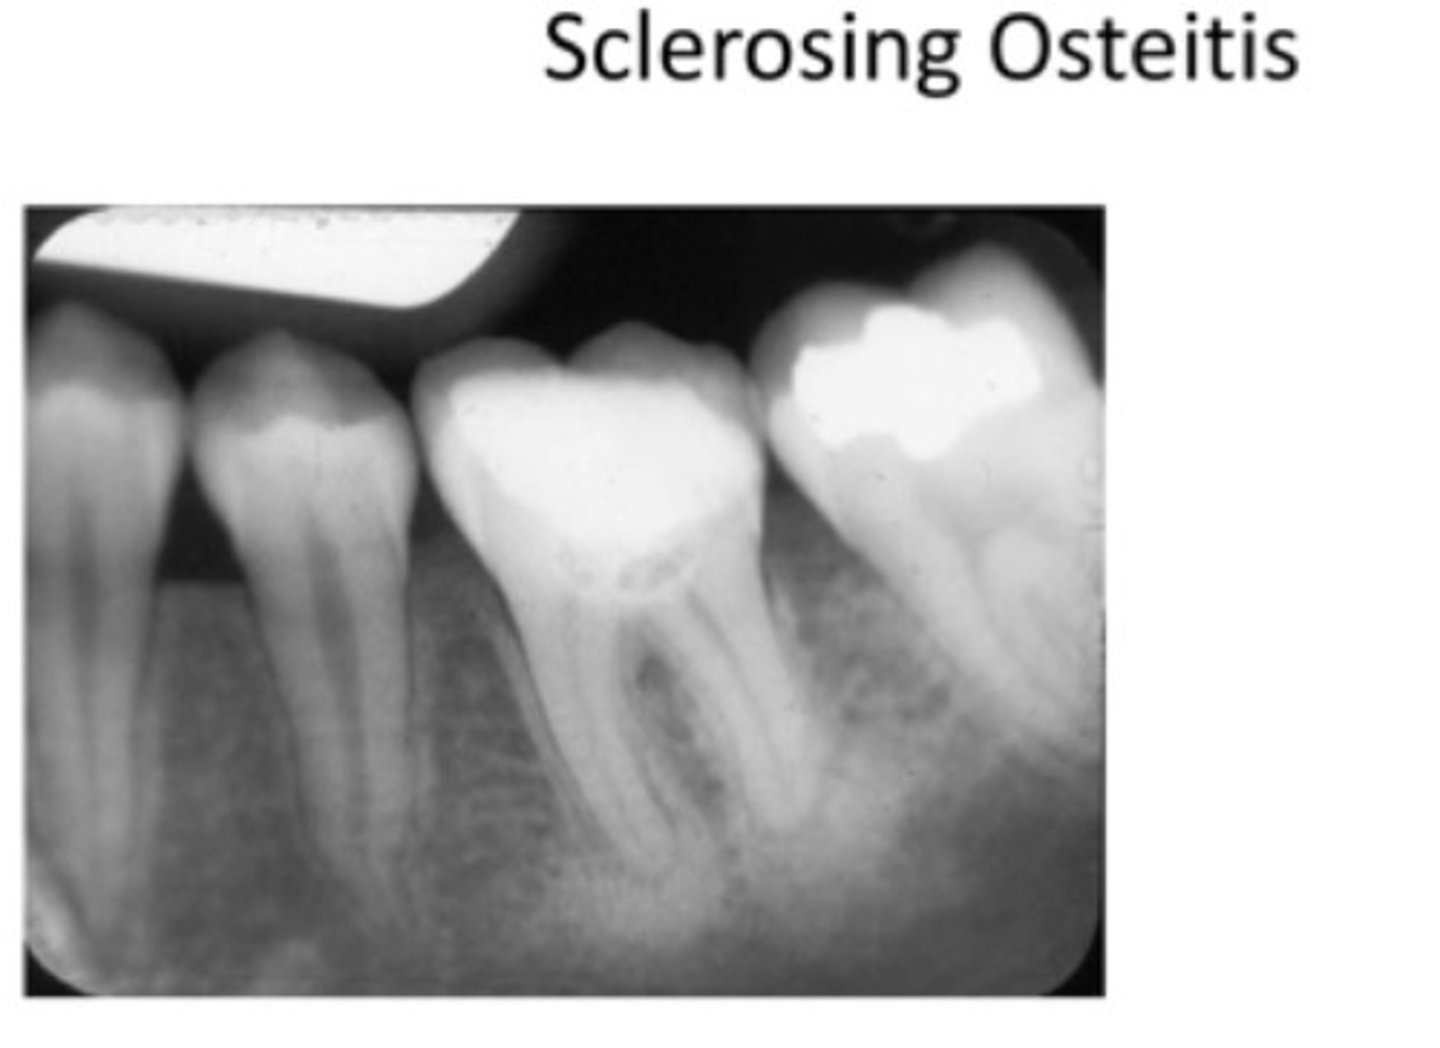

What is Periapical Sclerosing Osteitis also known as?

Condensing osteitis

What does Periapical Sclerosing Osteitis indicate?

Long standing infection